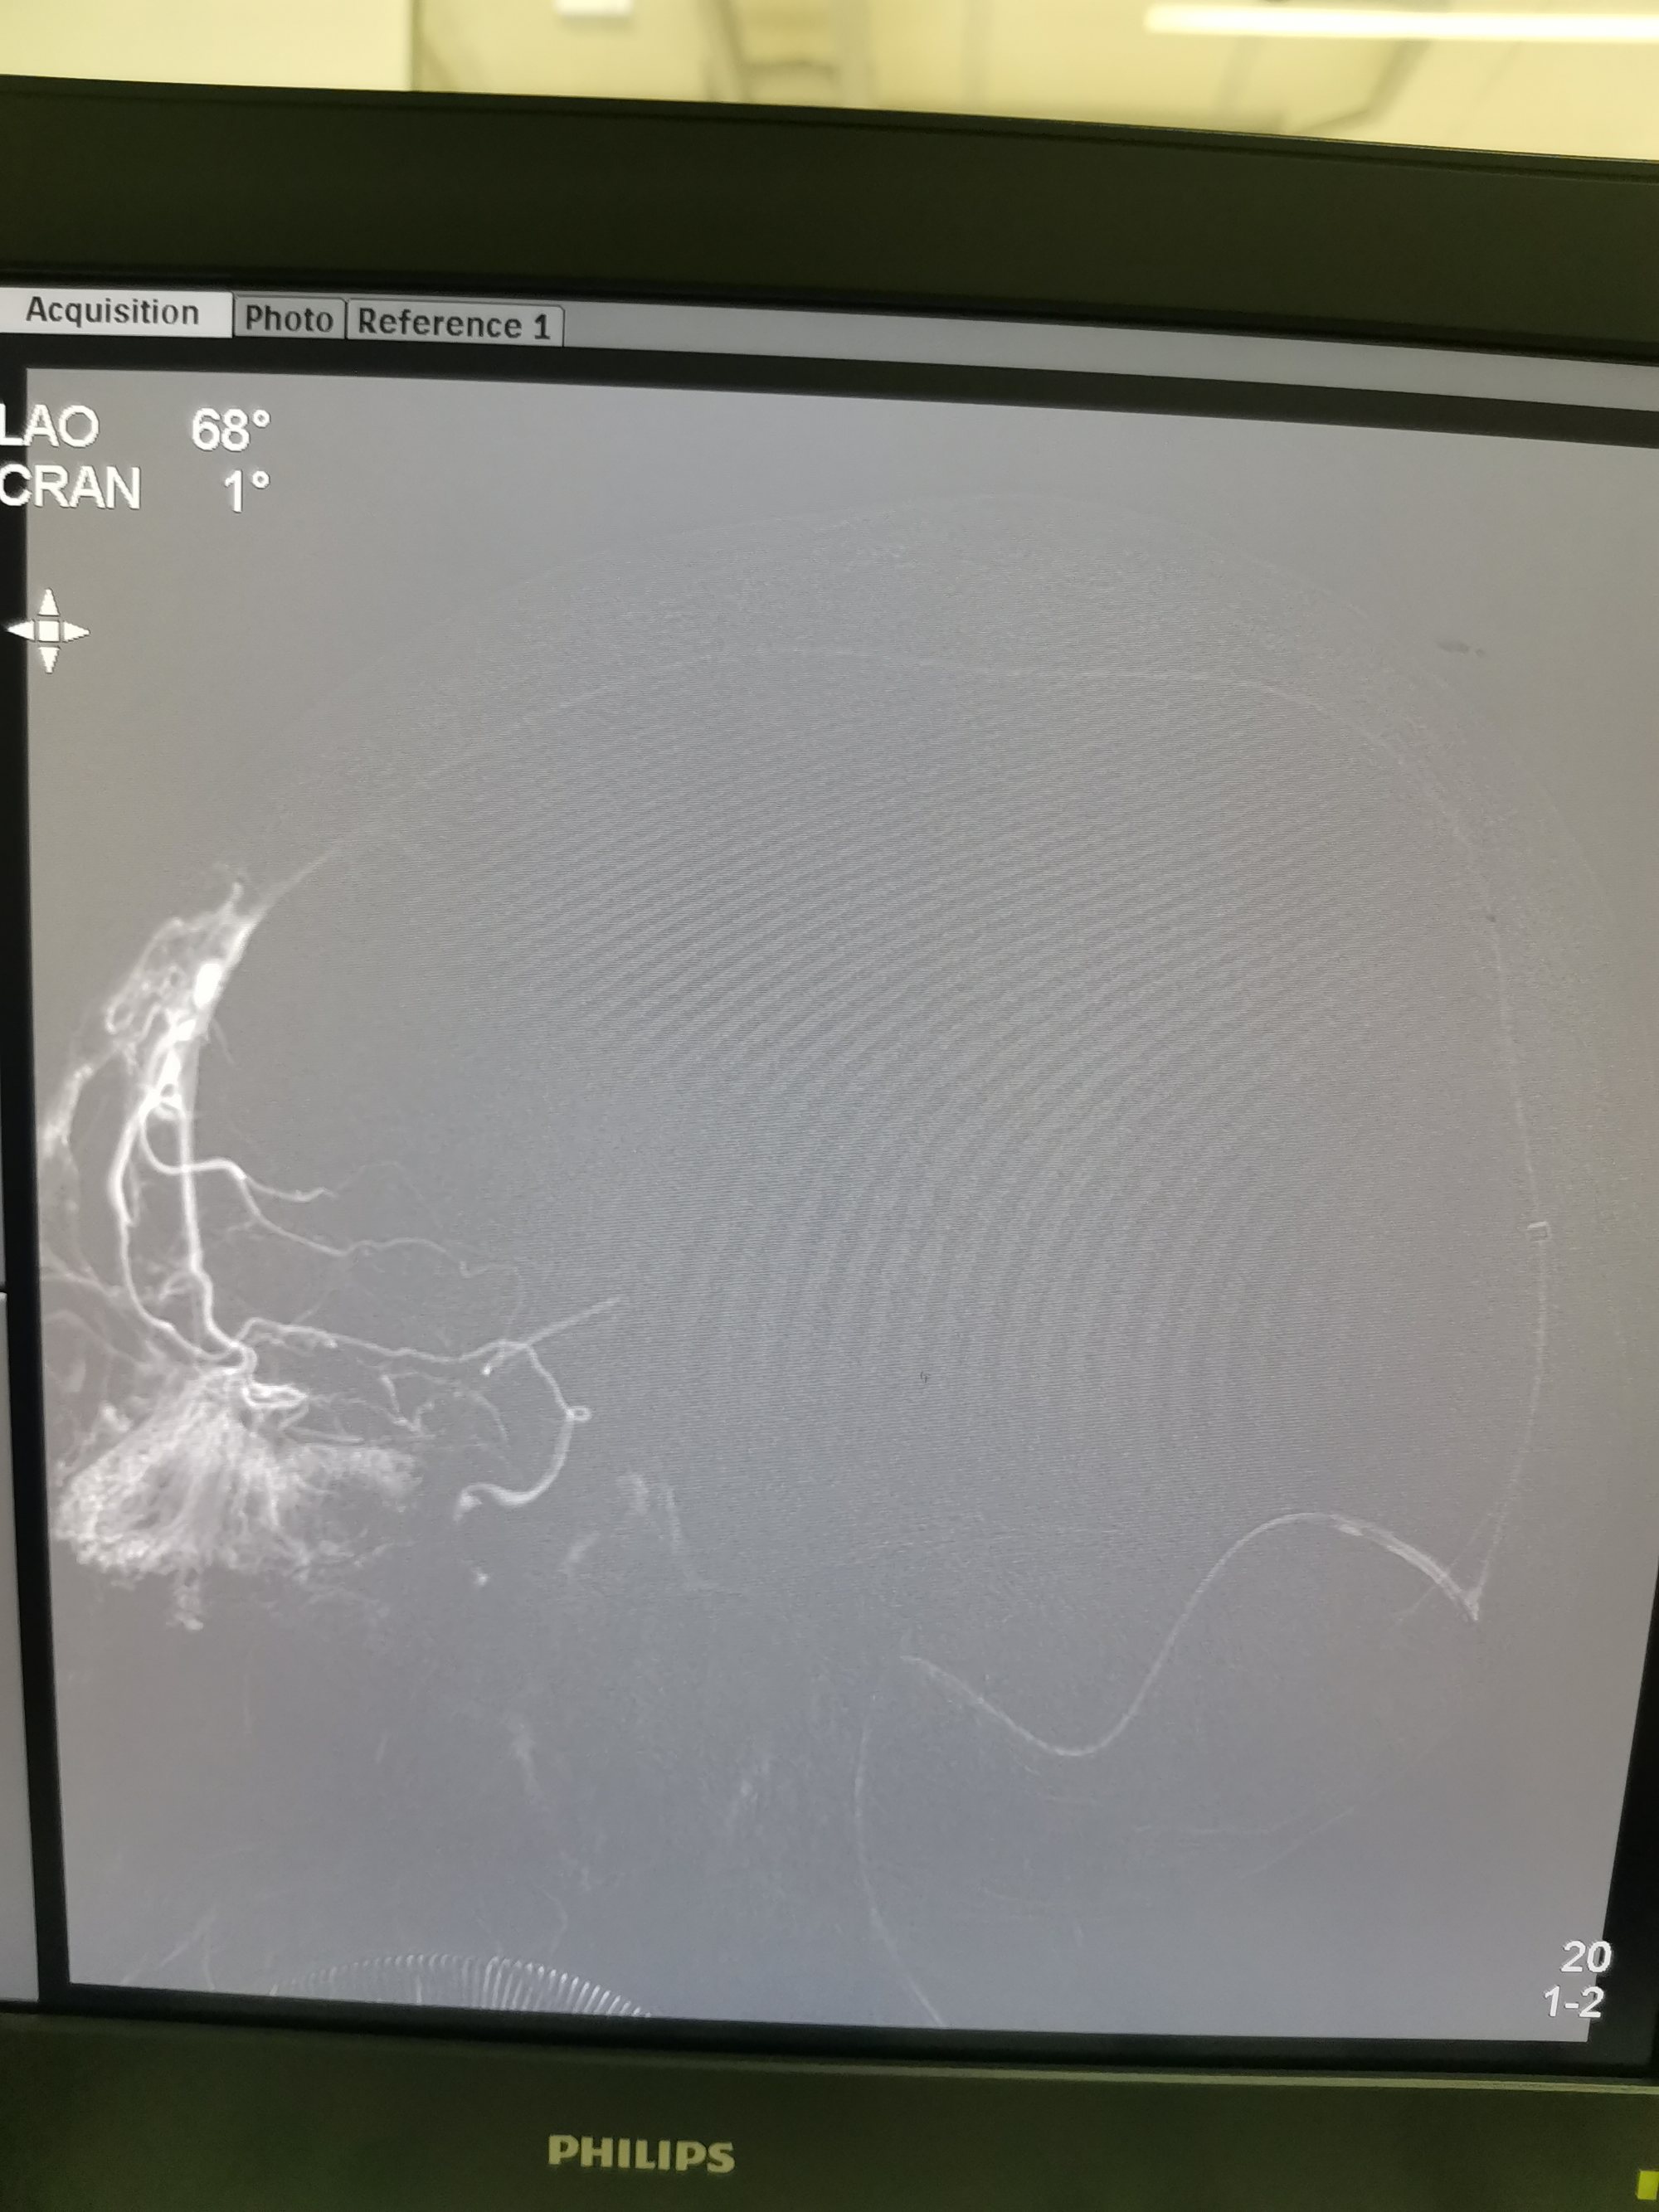

患者左侧横窦优势,左侧颈内动脉造影侧位见矢状窦起始部至横窦水平未显影。

抽吸导管上行过程中在横窦部位上行困难,抽吸无法抽出血栓。微导管在微导丝引导下到达矢状窦起始部位微导管造影见矢状窦起始部位血栓影,血流无法经矢状窦回流,经额极静脉逆向经颅底向颅外段静脉引流。